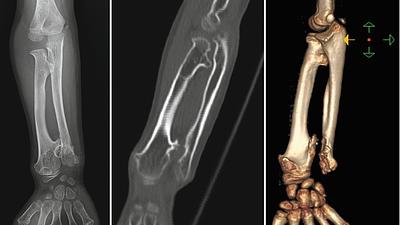

Radiologia é fundamental no diagnóstico precoce de tumores ósseos pediátricos

O osteossarcoma é responsável por aproximadamente 60% dos tumores ósseos malignos em crianças e adolescentes, com a maior incidência entre 10 e 20 anos de idade.